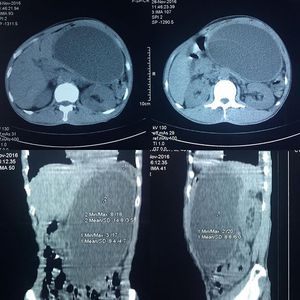

49 y.o male presenting with left abdominal mass, appeared following stab wound in left flank 2 months ago

The is no complains about defecating or urination. What seems to be the diagnosis ?